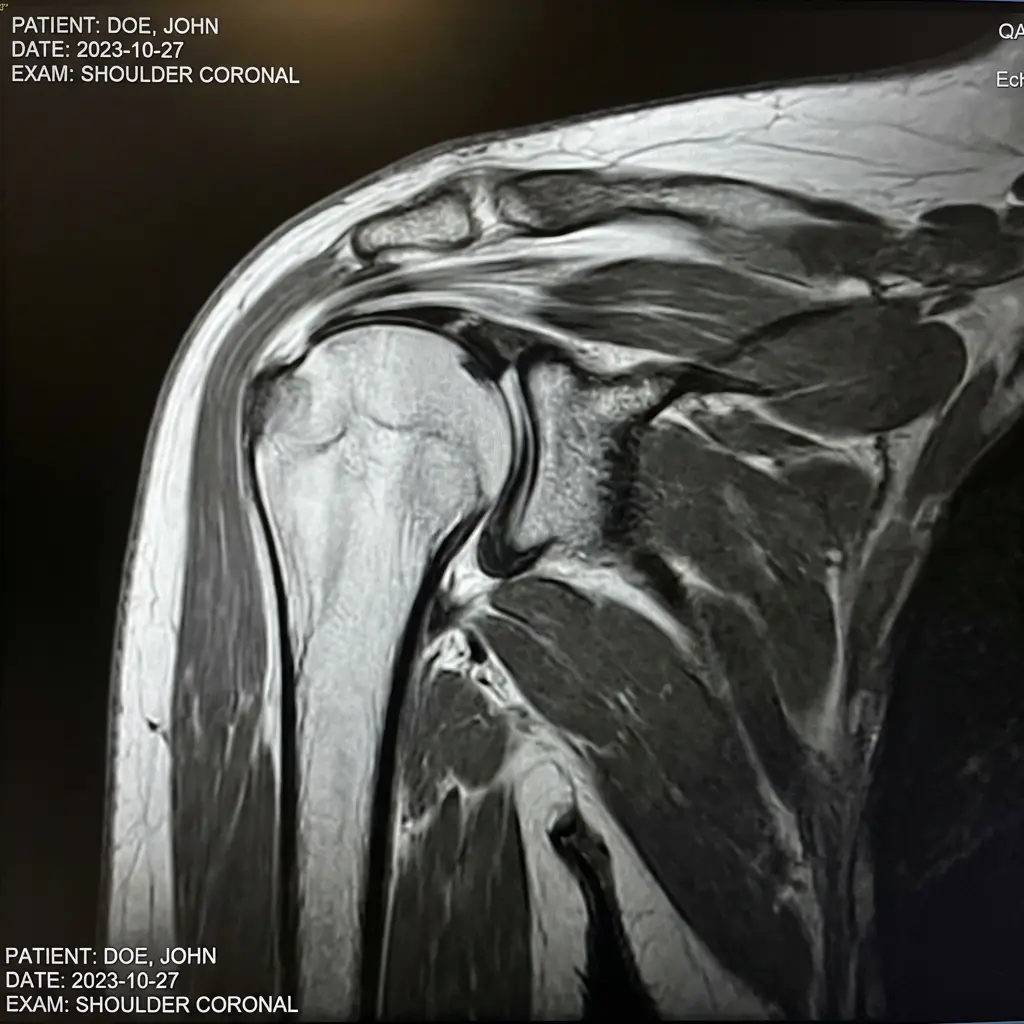

- Exames de imagem

Alguns exames podem confirmar o diagnóstico da lesão no manguito rotador, como:

- Ultrassonografia

- Ressonância magnética

- Raio-X

A ressonância magnética é considerada um dos exames mais precisos para avaliar o manguito rotador.